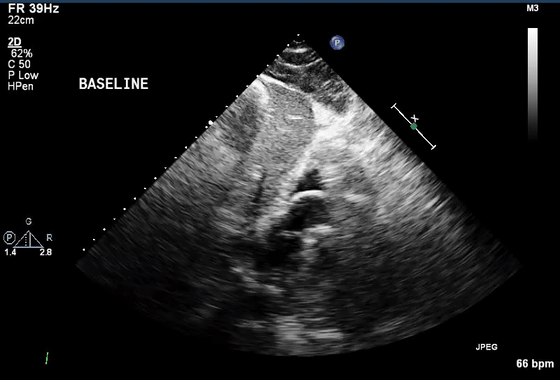

2、混响伪像

混响伪像违反了回波在一次反射后返回探头的假设。理论上,当超声波从探头发射时,反射波直接传输回探头,进行一次往返。实际上,第一次反回到探头的声波又从探头的平滑面再次反射,在两倍于第一反射器的距离处产生伪像。在心动周期期间,伪影的运动与真实结构的运动平行,但幅度更大(通常是两倍)(视频1-3)。

图2 (A,B)混响假象的理论成因(视频1)。第二反射界面可以是探头本身(A ),导致到探头两倍距离处的混响,或者是位于第一反射器上方的另一个强反射器(B)。

(C)胸骨旁长轴切面中的混响伪影似为左心房中的肿块(箭头)。对肿块的详细分析表明,它是钙化主动脉瓣环的反射(箭头),肿块正好出现在距离传感器两倍的距离处(视频2)。

(D)“多层”主动脉钙化(箭头)下方典型的“阶梯式”反射(实心箭头),作为第一和第二反射层(视频3)。也可以观察到强反射心包下的彗尾反射(空箭头)。